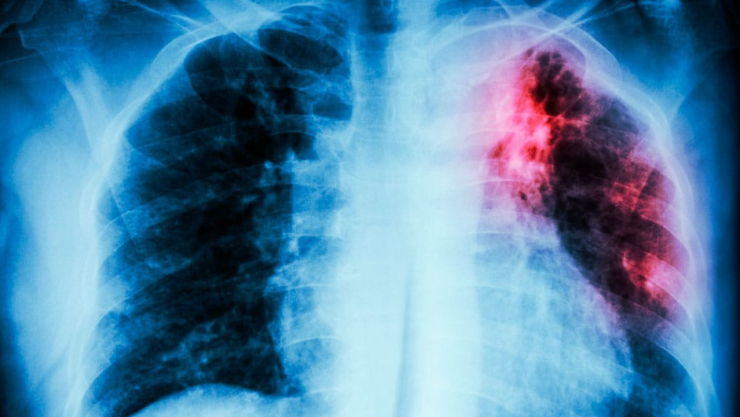

La tuberculosis es causada por la bacteria Mycobacterium tuberculosis, la cual se transmite por el aire cuando una persona infectada tose o estornuda. Los síntomas más comunes incluyen tos persistente por más de dos semanas, fiebre, sudoraciones nocturnas, pérdida de peso y dolor torácico.